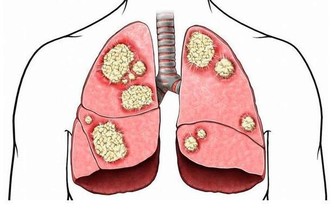

胃酸多、肚子脹、胃疼痛、消化不良、胃痙攣。唾液裡含有消化酶,可治療各種胃病,還可能殺癌細胞,但必須堅持經常利用,否則無效。每天用舌尖頂上牙齦或攪拌口腔夠一口就嚥下去,每天必須咽5-6次、每次咽5-6口唾液。